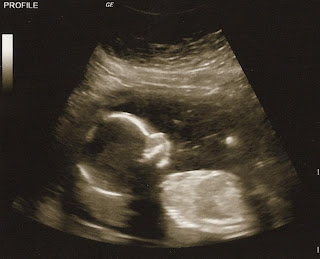

Things look great! The baby was somewhat uncooperative, laying face down - so I have to go back next week, hoping the baby flips - so that can get a better view of the heart. She was able to see most things - the heart rate was at 137, we saw all 4 chambers of the heart, the flow through the heart, the umbilical cord and blood flow, the liver, the kidneys, the stomach and bladder (with fluid in there - good things). She took shots of the brain and a bunch of measurements.... so that is all a big relief to me!

The picture looks a lot to me like our 11 week u/s:

The baby kept on waving it's hand around - too cute. To me it was crazy to see the baby moving around, but not be able to feel anything! The u/s tech was telling me that I should be feeling things soon.